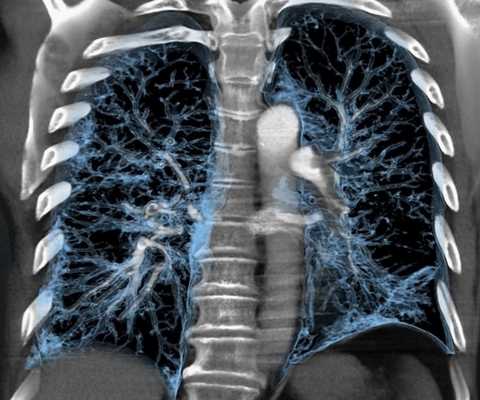

Мультиспиральная КТ грудной клетки, 3D-реконструкция

Современный высокоточный метод посрезового сканирования с использованием рентгеновского (x-ray) излучения и возможностью построения аутентичной 3D-модели костей, дыхательных путей, внутренних органов и сосудов. Преимущество компьютерной томографии заключается в том, что за несколько секунд томограф делает множество сканов, которые затем можно объединить в объемное изображение. Исследуют ткани любой морфологии: губчатую паренхиму легких, кости, органы.

При сканировании грудной клетки в область обзора попадают легкие, трахея, бронхиальное дерево, средостений, грудной отдел позвоночника и ребра. Для обследования сосудов и при подозрении на наличие онкологических опухолей проводится КТ грудной клетки с контрастом. Суть контрастирования заключается в том, что пациенту в плечевую вену предварительно вводится специальный препарат, который дополнительно «окрашивает» стенки сосудов и вен, а также позволяет визуализировать новообразования, уточнить их размер, а иногда и специфику (предварительно, для уточнения потребуется биопсия).